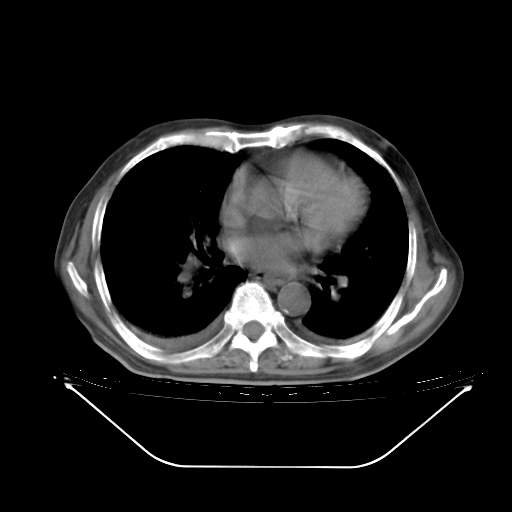

今天复查肺部CT,发现双肺广泛磨玻璃样改变。所以我把3月19日和5月9日相隔50天的肺部CT上传。请大家会诊。

5月9日肺部CT(在4月27日齐鲁医院肺部CT描述部分肺组织磨玻璃样改变,12天后肺组织广泛磨玻璃样改变)

2009年5月9日肺部CT